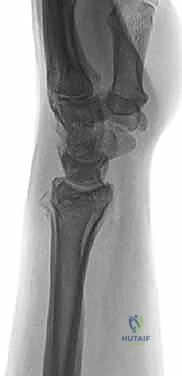

صورة طبية توضح كسر الناتئ الإبري

صورة لكسر في رأس الزند

استخدام الأشعة السينية في التشخيص

1. الأشعة السينية (X-rays): بوضعيات متعددة (أمامية خلفية، وجانبية دقيقة). الوضعية الجانبية الحقيقية (True Lateral) حاسمة لاكتشاف أي خلع جزئي في المفصل (DRUJ).

صورة طبية: علاج كسور عظم الزند: دليل شامل لكسور الناتئ الإبري، الرأس، والجزء الكردوسي الكردوسي مع الأستاذ الدكتور محمد هطيف في صنعاء